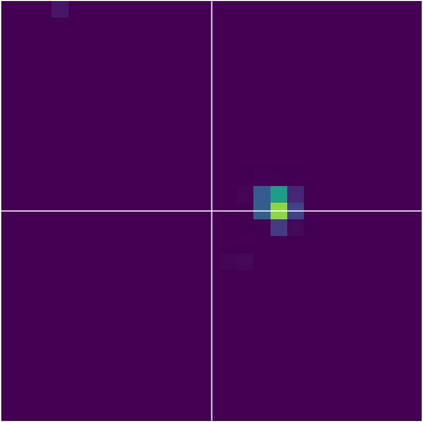

Various imaging modalities allow for time-dependent image reconstructions from measurements where its acquisition also has a time-dependent nature. Magnetic particle imaging (MPI) falls into this class of imaging modalities and it thus also provides a dynamic inverse problem. Without proper consideration of the dynamic behavior, motion artifacts in the reconstruction become an issue. More sophisticated methods need to be developed and applied to the reconstruction of the time-dependent sequences of images. In this context, we investigate the incorporation of motion priors in terms of certain flow-parameter-dependent PDEs in the reconstruction process of time-dependent 3D images in magnetic particle imaging. The present work comprises the method development for a general 3D+time setting for time-dependent linear forward operators, analytical investigation of necessary properties in the MPI forward operator, modeling aspects in dynamic MPI, and extensive numerical experiments on 3D+time imaging including simulated data as well as measurements from a rotation phantom and in-vivo data from a mouse.